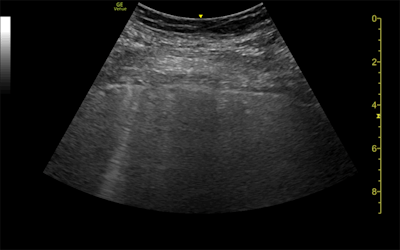

Ultrasound and CT images from a 62-year-old woman with long-term COVID-19 symptoms. The patient, who was not part of the study, visited the Madrid emergency department with persistent dyspnea and cough. The ultrasound image (above) shows an irregular pleural line and some B-lines, which correlate to ground-glass opacities in the lower lobes on CT (below). Images courtesy of Dr. Yale Tung-Chen, PhD.

The three patients in the study, which was published in the Journal of Ultrasound in Medicine, had mild cases of COVID-19 but lingering shortness of breath. Ultrasound scans revealed a variety of pulmonary findings, including irregular pleural lines and B-lines, which correlated with abnormalities on CT scans.

Ultrasound could be one alternative for these patients because the modality is both affordable and radiation-free. The authors also pointed to ultrasound's widespread availability, quick exam time, and ease of use in both medical and nonmedical settings.

However, ultrasound has its own drawbacks, notably limited sensitivity. This was especially evident in the case of the 35-year-old woman whose mild irregular pleural line on ultrasound corresponded not to abnormal pleura on CT but parenchymal tissue changes.